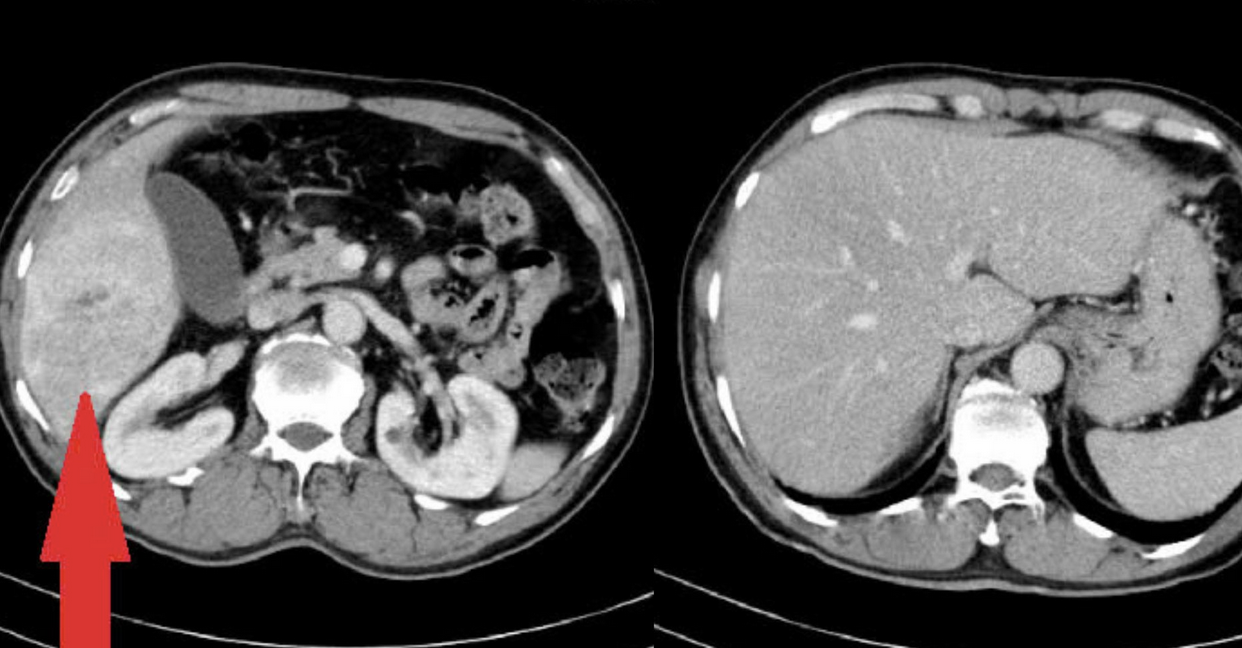

Thạc sĩ, bác sĩ Nguyễn Duy Anh, nguyên bác sĩ Trung tâm Ung bướu và Y học hạt nhân - Bệnh viện Bạch Mai, bác sĩ Trung tâm Ung bướu, Xạ trị và Y học hạt nhân Quốc Tế (Bệnh viện Đa khoa Phương Đông), cho biết trong quá trình thăm khám, bác sĩ đã từng tiếp nhận một trường hợp bệnh nhân nam (khoảng 70 tuổi tại Hà Nội) đi khám do đau tức vùng bụng, phát hiện khối ung thư gan phải kích thước lớn.

Sau quá trình thăm khám và xét nghiệm, người bệnh được chẩn đoán mắc ung thư biểu mô tế bào gan – giai đoạn tiến triển. Bệnh nhân được điều trị liệu pháp toàn thân (truyền “thuốc kháng thể đơn dòng kết hợp thuốc miễn dịch” 3 tuần 1 lần). Quá trình điều trị hiệu quả, giai đoạn ung thư giảm từ tiến triển thành trung gian và sau đó đã phẫu thuật cắt được u.

Em gái của bệnh nhân ở nhà cũng đau bụng, vàng da, vàng mắt. Khi đi khám, người này phát hiện ung thư gan giai đoạn muộn hơn. Cô cũng được điều trị liệu pháp toàn thân, nhưng khối u ở vị trí trung tâm của gan, xâm lấn vào ống dẫn mật chính nên không thể phẫu thuật như anh trai, bác sĩ Duy Anh nói.